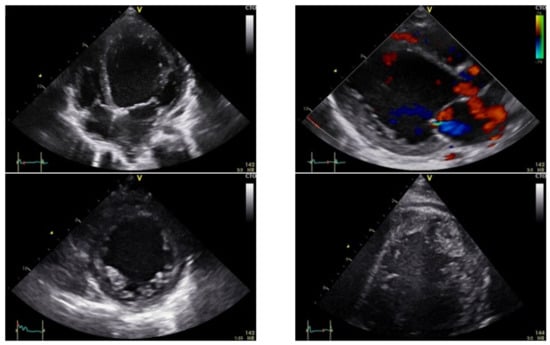

| HR | 100/min | 50/min | Pump Stop 5 min |

|---|---|---|---|

| VTI aortal | 10 cm | 15–20 cm | 20 cm at 100/min |

| EF Simpson | 30% | 25% | 30% |

| LVEDD | 47 mm (+1.3 Z) | 42 mm (+0.23 Z) | 51 mm (+2.8 Z) |

| LVEDV RT3DE | 88 mL/m2 | 100 mL/m2 | |

| GLS4Ch | −6% | −6% |

| Echocardiographic Parameters (Echo) | Left ventricular end-diastolic diameter (LVEDD) |

| LV EF, optional RV- EF | |

| Velocity time integral aortal and pulmonal (VTI’s) | |

| LVEDV, LVESV-RT3DE | |

| dp/dt MI (Mitral insufficiency), TAPSE | |

| Deformation parameter with speckle tracking method (ST) | |